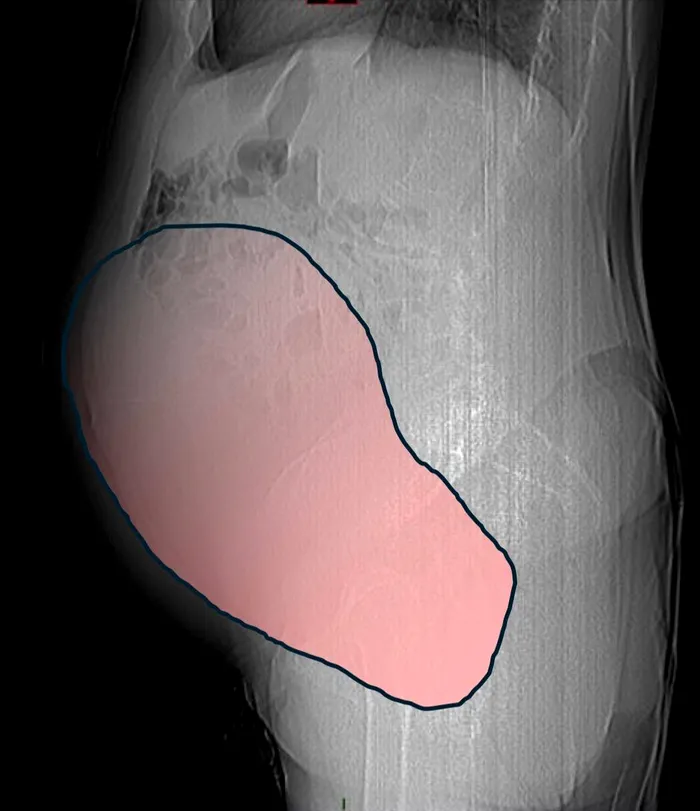

Timp de luni de zile, chistul ovarian gigant, cu un diametru de aproximativ 28 de centimetri, a rămas ascuns, fără a da semne evidente. Pacienta nu observase nimic.

Alarma a fost dată când masa, asociată cu prezența unui al doilea neoplasm intestinal, a început să comprime colonul, provocând dificultăți intestinale severe.

În timpul operației, gravitatea situației a devenit evidentă. Tumora ovariană gigantică a fost îndepărtată: cântărea aproximativ 6 kilograme, având un volum comparabil cu cel al unei sarcini gemelare la termen. Cele mai periculoase simptome erau legate de tulburările intestinale, care necesitau intervenția imediată și coordonată a mai multor specialiști.